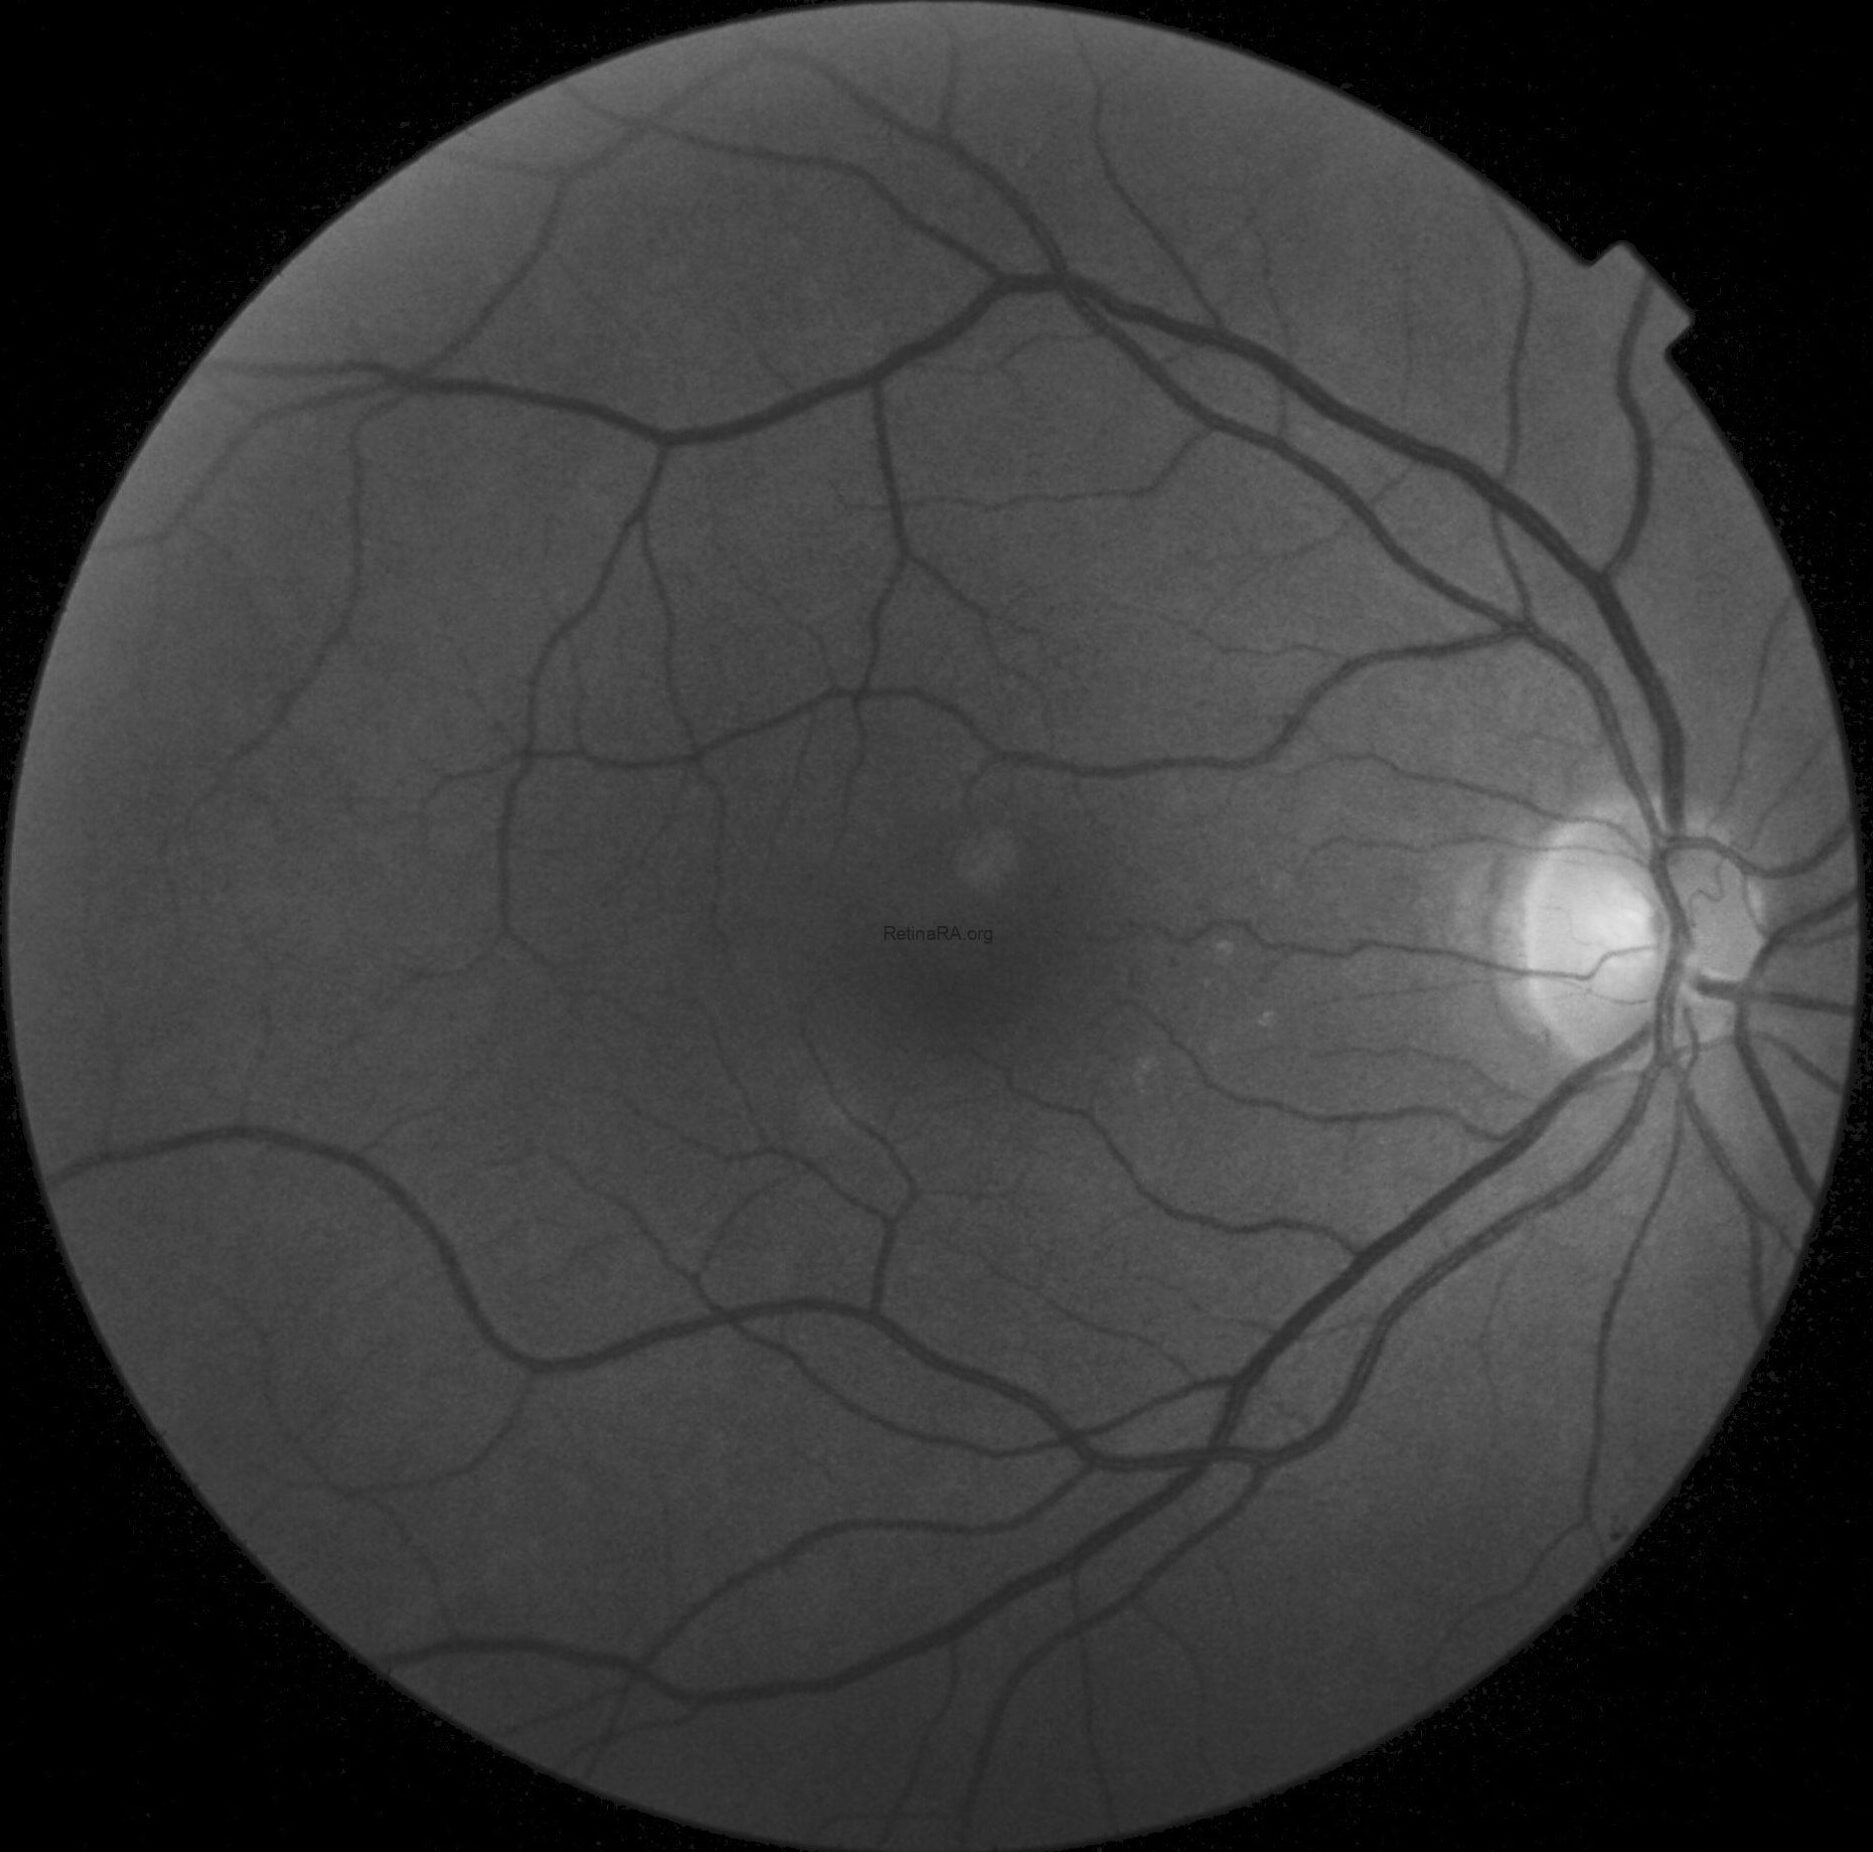

Color fundus photography in OD revealed mild RPE dystrophy in the nasal macular region and a crescent zone of temporal peripapillary chorioretinal atrophy consistent with glaucomatous beta-zone.

CFP in OS, however, showed marked optic nerve pallor associated with glaucomatous beta-zone temporal peripapillary atrophy, baring of circumlinear blood vessels and an extensive anomalous macular reflex, starting from the temporal edge of the optic disc and proceeding up to the perifoveal region, ultimately extending around the fovea itself.

These findings are better highlighted with red-free photography, which demonstrates a full encircling of the fovea by the anomalous reflex and furthermore displays extensive RNFL defects in the left eye when compared to the right eye.